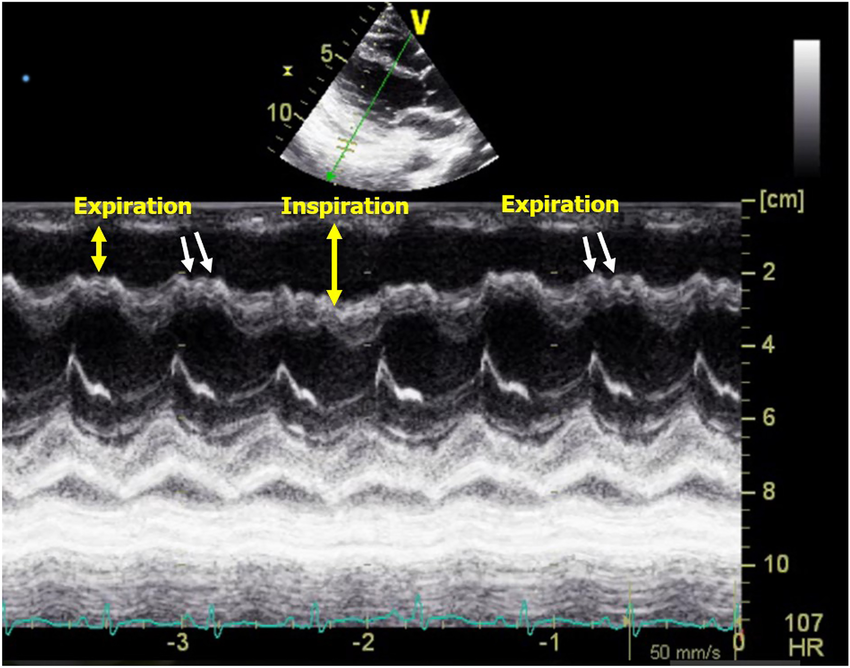

Constrictive pericarditis

What condition is seen in the following m-mode image?